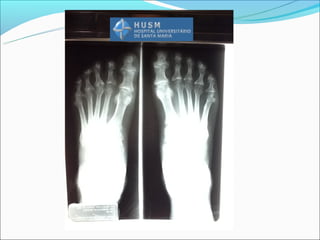

Sídrome de Reiter

Alterações idênticas a

AP

Pés mais afetados que as

mãos

Interfalângicas do hálux

é a mais acometida

Novo osso e esporão

mal definidos